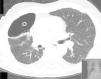

This time, instillation of methylene blue (1 ampoule diluted in 1 liter saline solution) via chest tube was used to locate the bronchial segment leading to the fistula. While the blue solution was being instilled another clinician looked through the bronchoscope and watched the blue solution appearing on the segments leading to the fistula. Segments B6 and B7 were visually identified (Fig. 3) and endobronchial valves were put in place as described above.

In our patient the use of methylene blue enabled identification of two bronchial segments involved in the air-leak, one common to that identified by the balloon method but also a different one unsuspected by the previous technique.